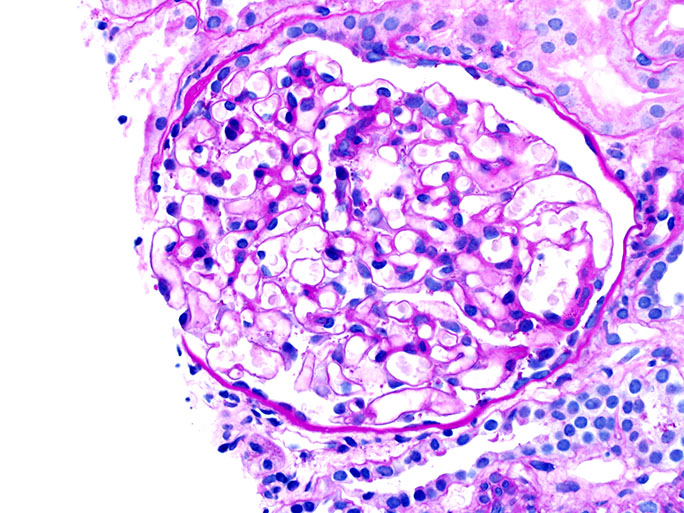

2. Periodic Acid Schiff or PAS: stains carbohydrates and carbohydrate rich macromolecules including collagen a deep red or magenta color

A kidney pathology tip to identify a hypercellular glomerulus: try the chocolate chip cookie analogy (i.e. more chips = more cells)